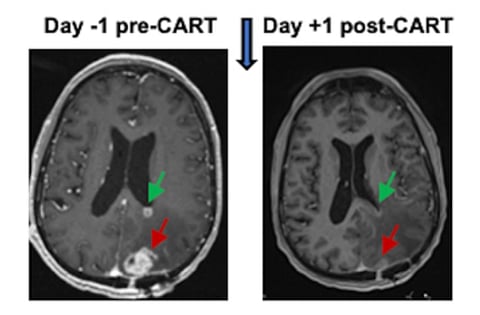

Las resonancias magnéticas cerebrales de los seis pacientes inscritos en el ensayo mostraron reducciones rápidas del tumor que ocurrieron dentro de uno o dos días después del tratamiento.

La estrategia pareció funcionar: las resonancias magnéticas tomadas solo 24 y 48 horas después de la administración de CAR-T mostraron una notable reducción de los tumores.

"Estas reducciones se han mantenido hasta varios meses después en un subconjunto de pacientes", dijeron los investigadores de la UPenn.